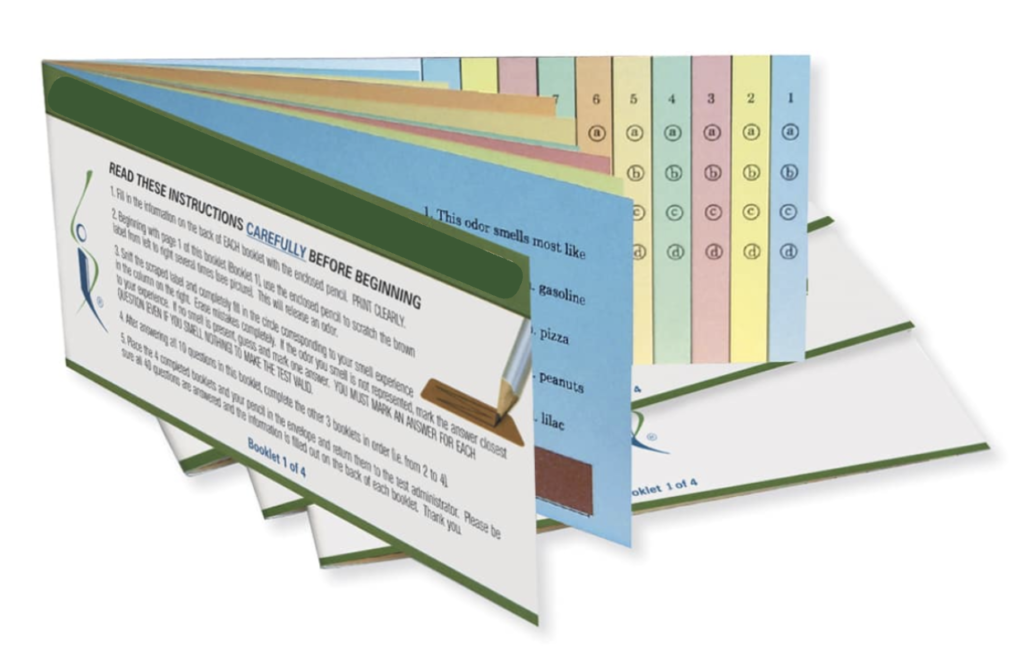

Evaluación del sentido del Olfato

Tras la pandemia de COVID-19 en 2020, se obtuvo una importante comprensión sobre el papel del sentido del olfato en las condiciones neurológicas. El olfato es un sentido que ha permanecido en gran medida inalterado a lo largo de la evolución humana. El nervio olfatorio, responsable de transmitir los estímulos olfativos a centros cerebrales específicos, puede verse afectado durante la infección por COVID-19, incluso en individuos asintomáticos.

Muchas enfermedades neurodegenerativas, como la enfermedad de Parkinson, pueden comenzar décadas antes de su manifestación clínica. Diferenciar la enfermedad de Parkinson de otras condiciones con síntomas similares es esencial para un tratamiento y pronóstico adecuados.